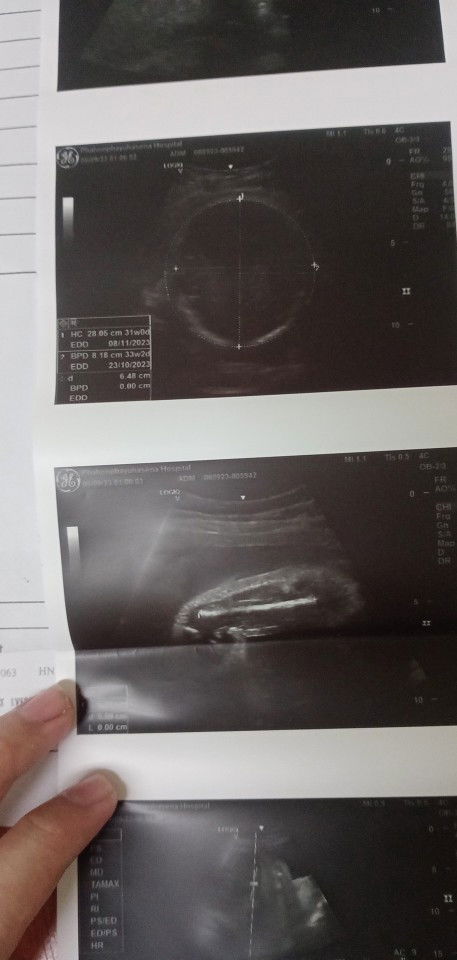

30วีค 3วัน น้ำหนักน้อง2000กรัม

ขอสอบถามแม่ๆหน่อยค่ะพอดีหนูได้แอดมิทที่โรงพยาบาลคุณหมออัลตร้าซาวด์น้ำหนักน้อง2000กรัมน้อยไปไหมคะ#ขอคำแนะนำหน่อยค่ะ #ขอบคุณสำหรับคำตอบค่ะ 🤍